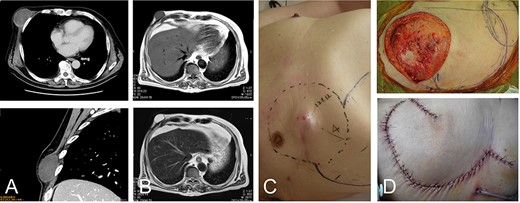

76-year-old male with recurrent myxofibrosarcoma. Computed tomography revealed the initial 6-cm subcutaneous lesion of the patient at 73 years of age (A); 3 years after resection of the initial lesion, T1- and T2-weighted images show a 3-cm recurrent lesion with high-signal intensities (B-upper) and (B-lower), respectively. Photograph showing protuberant subcutaneous lesion (C); defect after resection of the tumor with the surrounding tissue (D-upper). The defect was reconstructed with a thoracoabdominal flap (D-lower).

A 73-year-old man presented with complaints of a mass on her right chest wall for several months. Physical examination revealed a 6-cm elastic mass on her anterior chest wall that ranged from soft to hard on palpation. Computed tomography showed a subcutaneous tumor that was 6 cm in diameter (Fig. 2A). Histological examination of a biopsy specimen revealed a myxofibrosarcoma. The tumor was resected with the skin over the tumor, and the wound was closed without reconstruction. After 3 years of the initial operation, the 76-year-old patient underwent MRI, which revealed a recurrent lesion of 3 cm in diameter showing homogenous low-signal intensity on the T1-weighted image and homogenous high-signal intensity on the T2-weighted image (Fig. 2B).

The tumor was resected along with more than 4 cm of surrounding underlying pectoralis major muscle and the skin and subcutaneous tissue, resulting in a defect of greater than 12 cm in the maximum diameter. The defect was reconstructed by the same method used in Case 1 for placing a medially-based thoracoabdominal flap (Fig. 2C andD). The patient’s shoulder showed free range of movement. The patient has remained free of tumor over a 4.5-year postoperative period.